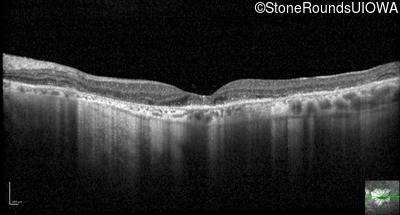

Optical Coherence Tomography - Right - 10/140

Exemplar / OCT Stack